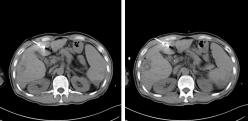

今年4月,張叔上腹增強CT檢查顯示:肝硬化,肝門區及腹主動脈旁淋巴結增多、部分增大,結合患者多年乙肝肝硬化病史,診斷為“發性肝癌IV期”。張叔早知他是乙肝患者,但不曾料到自己正值壯年就已患上肝癌。經同鄉介紹,今年6月,張叔來到廣州復大腫瘤醫院進行氬氦刀冷凍消融術及肝門靜脈癌栓125碘粒子植入術,術程順利,手術創口僅約2mm,術后患者感覺良好,生命體征平穩,治療效果良好,隨即出院返回四川鄉下(詳情百度搜索:廣州復大醫院案例)。

12月初,張叔再次來到醫院就診??紤]肝左葉腫瘤性病變。綜合患者各項生理指標,為控制腫瘤病灶的進一步增大,以牛立志教授為首的專家團隊建議他進行微波消融治療。因為張叔的血小板只有5萬多,而氬氦刀冷凍消融會消耗血小板,這種情況出血風險比較大,而微波消融對血小板影響小,對肝硬化失代償的患者來講可以爭取更多的抗腫瘤治療機會。

12月14日張叔在B超加CT引導下行肝臟腫瘤微波消融治療,過程順利,術中消融區域定位準確,消融范圍滿意,術后未訴不適,生命體征平穩,術后恢復良好,并且在術后第三天出院回家。